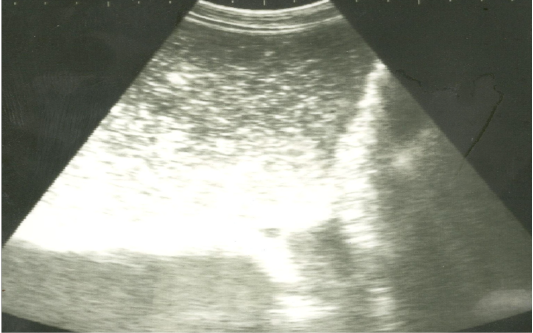

Ultrasonographic image of the left abdomen of horses with colic associated with impaction of the intestineusing 3.5 MHz transducer. There was marked distension of the descending colon with ingested materials that appeared hypo to hyperechoic. The intestinal loop diameter exceeds 8 cm.